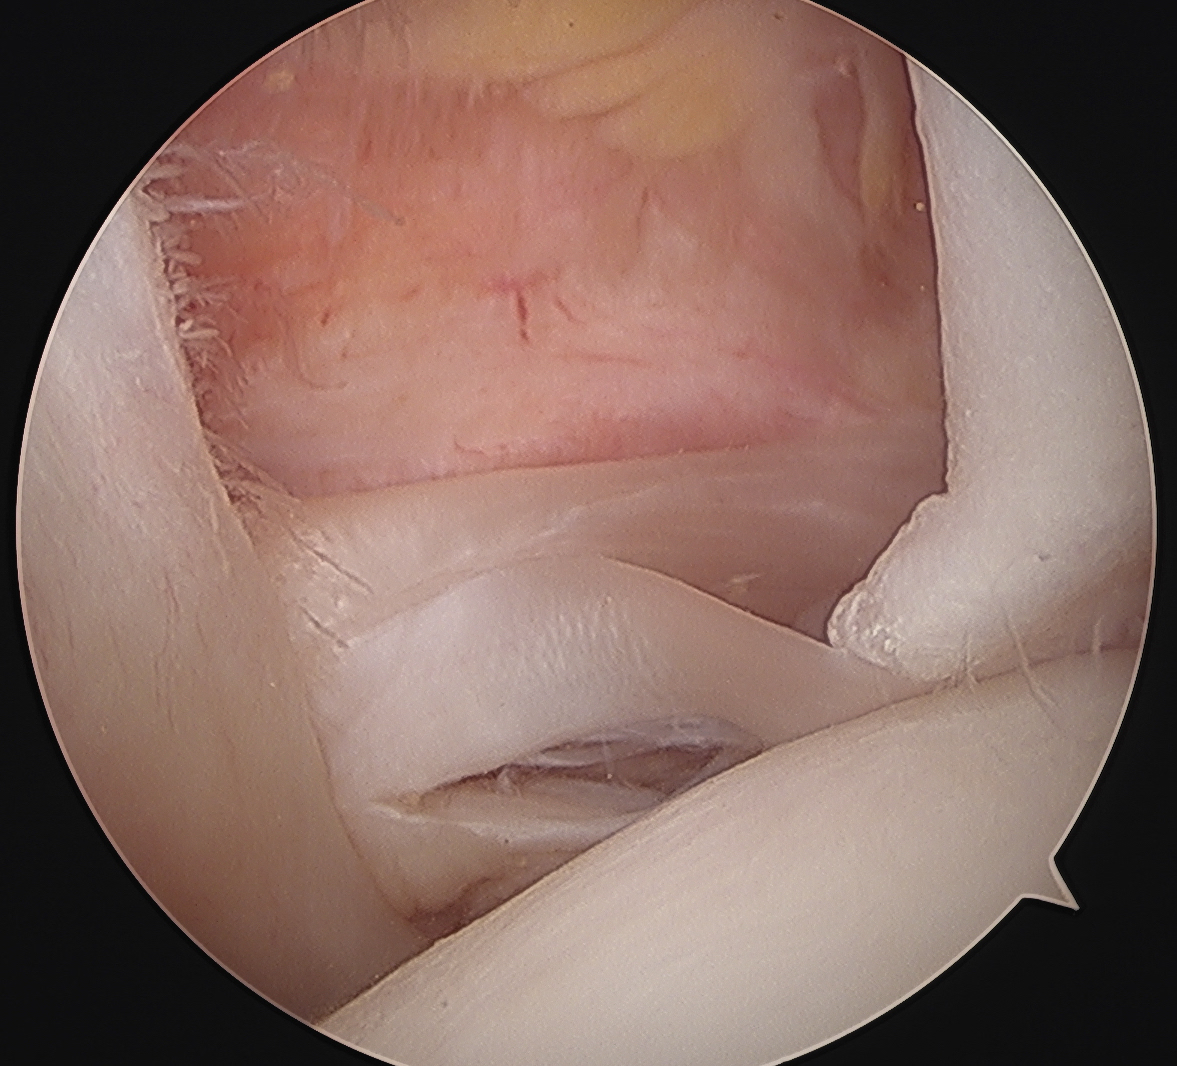

Medially dislocated biceps tendon with upper border subscapularis tear

Full thickness tear of subscapularis off insertion revealed with grasper